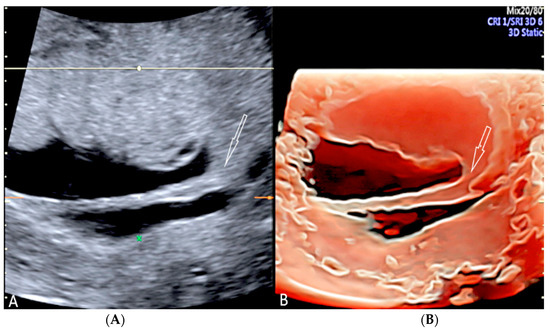

3.1.4. Circumvallate Placenta

- Arlicot, C.; Herve, P.; Simon, E.; Perrotin, F. Three-dimensional surface rendering of the chorionic placental plate: The “Tire” Sign for the diagnosis of a circumvallate placenta. J. Ultrasound Med. 2012, 31, 337–341. [Google Scholar] [CrossRef]